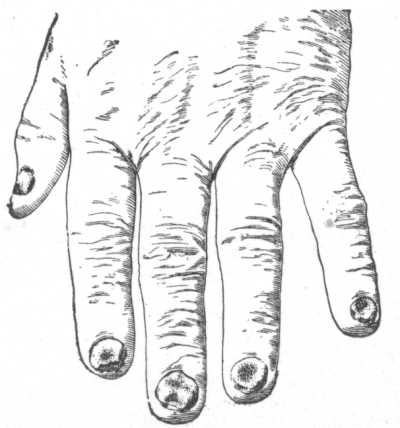

Fig. 11.

Erythema Multiforme, in which many of the lesions have become bullous—

Erythema Bullosum.

What type of the eruption is most common?

The papular, appearing usually upon the backs of the hands and forearms, and not infrequently, also, upon the face, legs and feet. The papules are usually pea-sized, flattened, and of a dark red or violaceous color.

Describe the various shapes which the erythematous lesions may assume.

Often the patches are distinctly ring-shaped, with a clear centre— erythema annulare; or they are made up of several concentric rings, presenting variegated coloring—erythema iris; or a more or less extensive patch may spread with a sharply-defined border, the older part tending to fade—erythema marginatum; or several rings may coalesce, with a disappearance of the coalescing parts, and serpentine lines or bands result—erythema gyratum.

Does the eruption of erythema multiforme ever assume a vesicular or bullous character?

Yes. In exceptional instances, the inflammatory process may be sufficiently intense to produce vesiculation, usually at the summits of the papules—erythema vesiculosum; and in some instances, blebs may be formed—erythema bullosum. A vesicular or bullous lesion may become immediately surrounded by a ring-like vesicle or bleb, and outside of this another form; a patch may be made up of as many as several such rings—herpes iris. In the vesicular and bullous cases the lips and the mucous membranes of the mouth and nose also may be the seat of similar lesions.